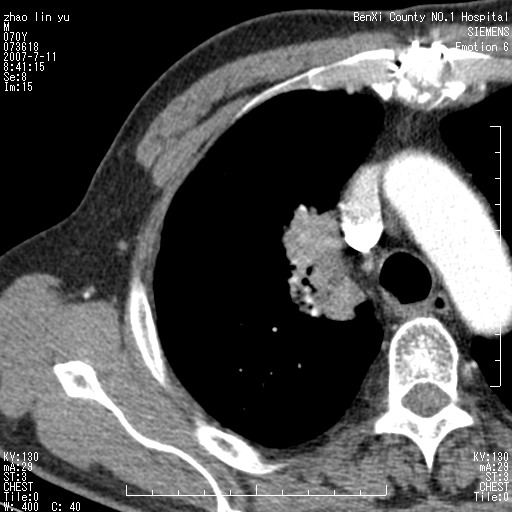

以下是引用王靖旗在2007-7-10 17:12:00的发言:[br] 男、70、咳嗽两个月,半年前换瓣手术,胸片未见异常,于昨天行x片发现右肺上野大片影,行ct扫描,这里是减薄图像,余肺正常。明天晚上会有增强扫描片,到时我会上传。[br][br] 冠状位请大家细看,应该是有意义的,[br][br] 请大家先看平扫发表意见。[br][br]

以下是引用zhangzhongshou在2007-7-10 21:43:00的发言:[br]右肺上叶周围型肺癌,以孤立型细支气管肺泡癌可能性大。